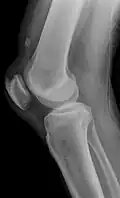

X-ray of a tear of the patellar tendon. On the left: The kneecap is pulled up. On the right: Significant dent in the soft tissue above the kneecap. -